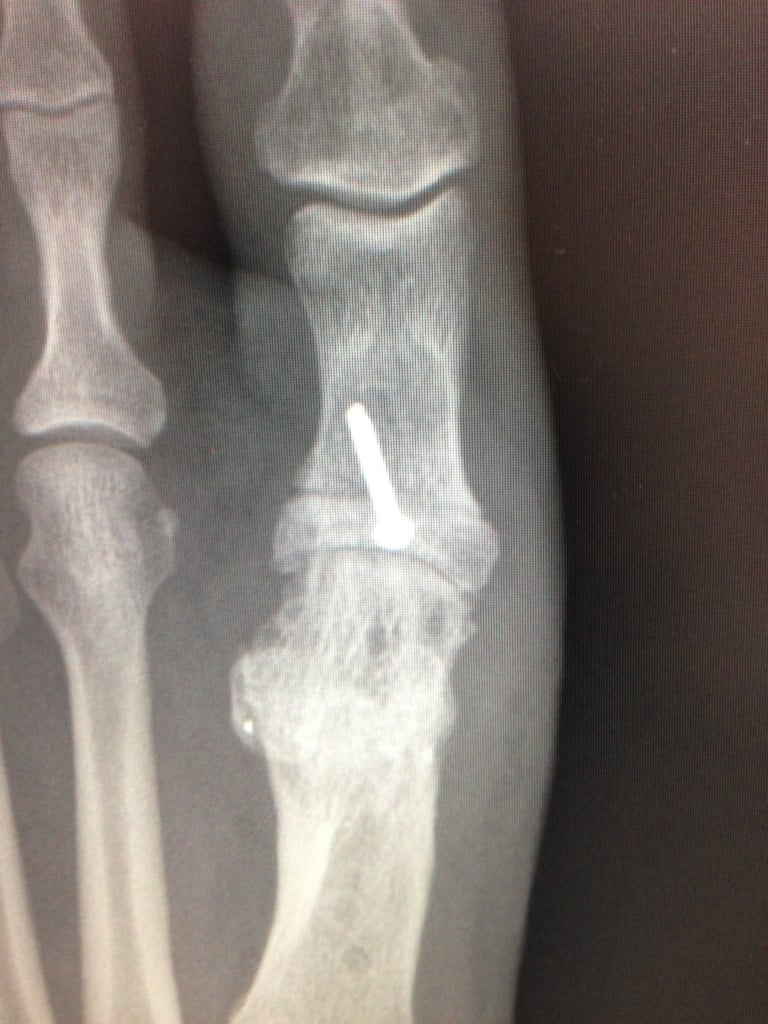

That is when I went to HSS and met Dr. Martin O'Malley. Essentially, the first "Podiatrist" had removed too much bone from my foot causing a non-union of the bone. Dr. O'Malley suggested removing healthy bone from my hip and inserting it into my foot to re-grow and re-join the bone. It was a long road, and I was well informed it would be. I was in bed for weeks post surgery, then non weight bearing for a month followed by crutches and a boot for almost 8 months. I was very active in paddle tennis and exercise, and truly thought I would never perform these luxuries again.

However, under the careful guidance of Dr. O'Malley and two additional surgeries; one to remove the screw and broken titanium plate followed by a Moburg Hallux Rigidus repair, I finally started getting my life back. Slowly but surely my foot began to act "normal" and I was able to resume activities including becoming a certified Yoga Instructor. Dr. O'Malley essentially put humpty dumpty back together again! I am forever grateful for not only his knowledge and kindness, but everyone at HSS for their unprecedented quality of care.